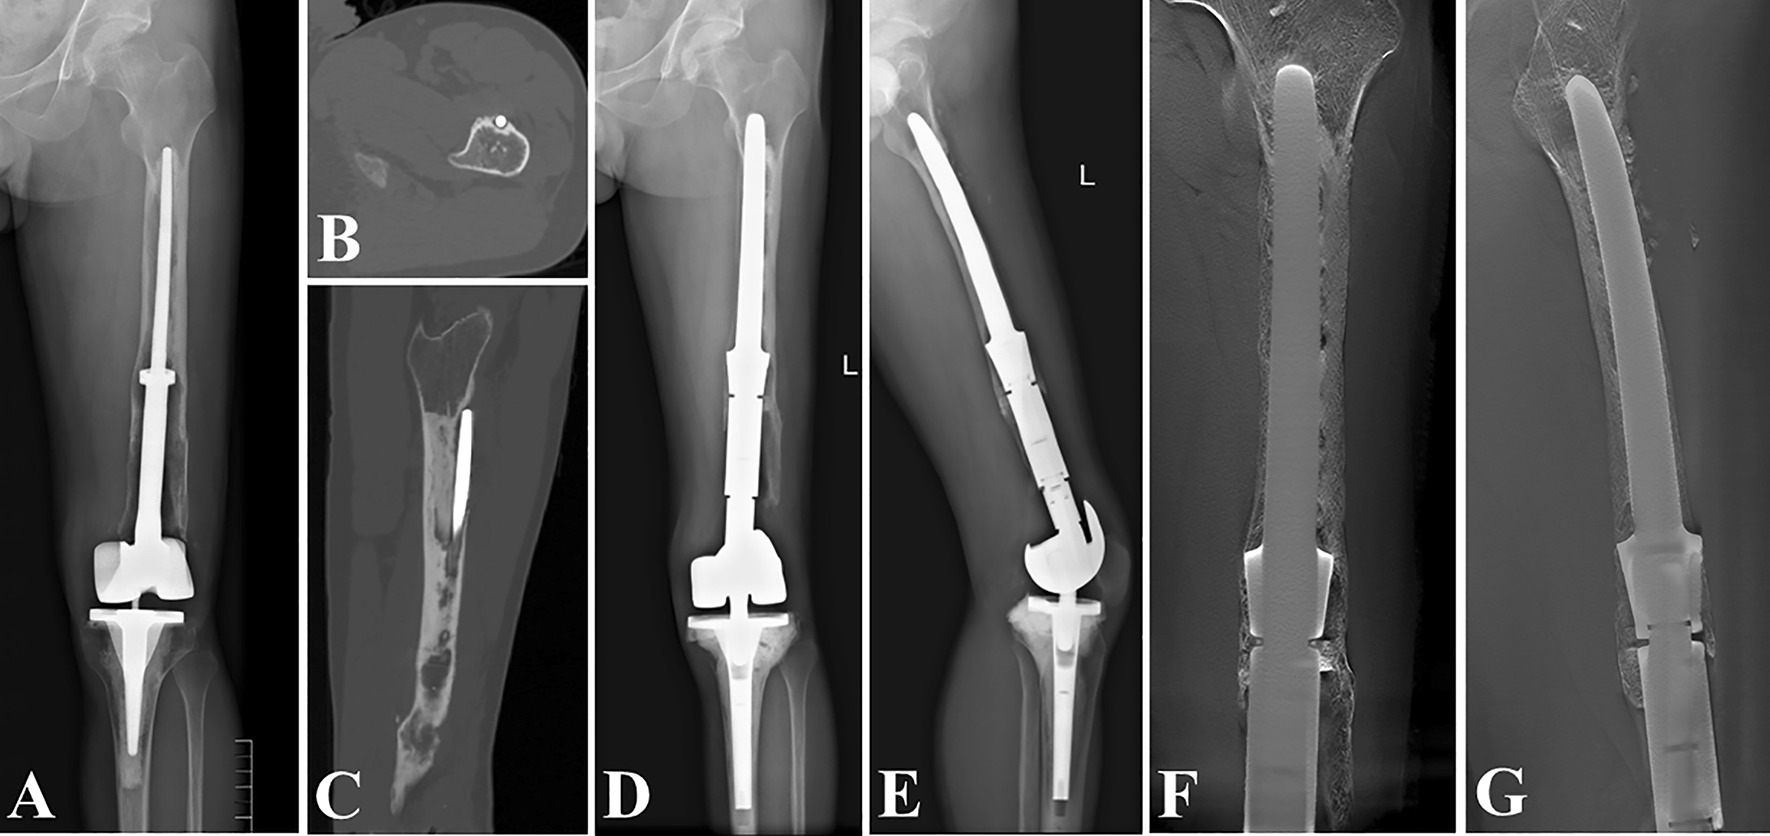

Fig. 5.

Revision of a Grade III bone loss case with “Ultra-long uncemented stem”. A, B preoperative radiographs; C the digital tomosynthesis image 6 months after revision surgery; D the surrounding hyperplastic tissue photograph; E the initial cemented endoprosthesis photograph

Fig. 6.

Revision of a Grade IV bone loss case with “Intra-neck curved uncemented stem”. A preoperative radiograph; B intraoperative photographs; C postoperative radiograph 6 months after the revision surgery; D function photographs